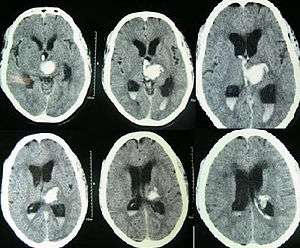

![]() | |

| Hydrocephalus as seen on a CT scan of the brain. The black areas in the middle of the brain are abnormally large and filled with fluid. | |